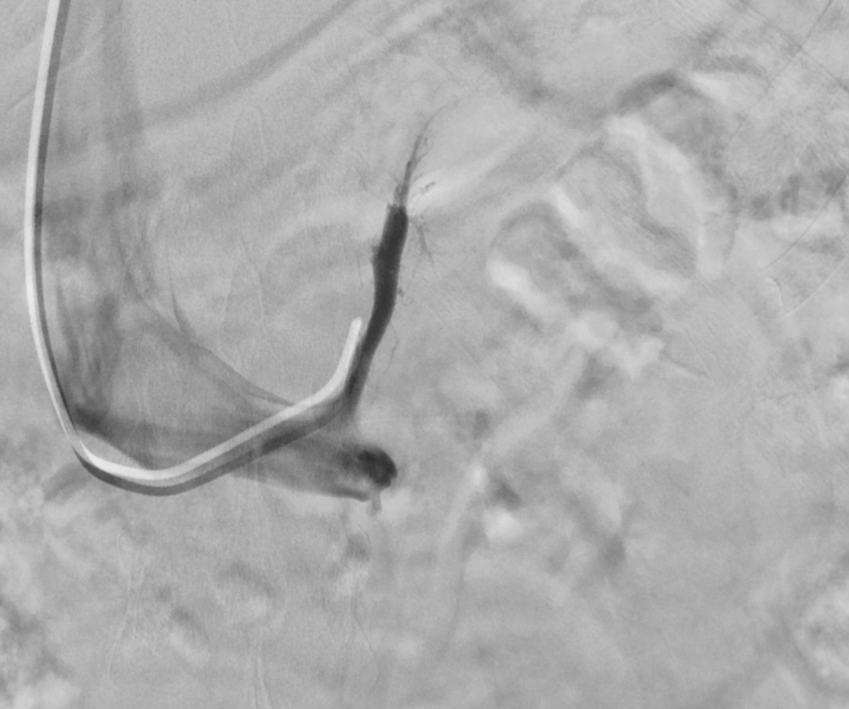

双侧肾上腺静脉取血提示右侧肾上腺为优势分泌侧。经与泌尿外科充分术前讨论,鉴于其右侧腺瘤体积较小,且合并左侧增生,外科手术切除腺瘤较困难,且患者拒绝外科手术治疗,故予右侧肾上腺动脉栓塞治疗。

(历时30分钟成功施行经皮选择性肾上腺动脉栓塞术)